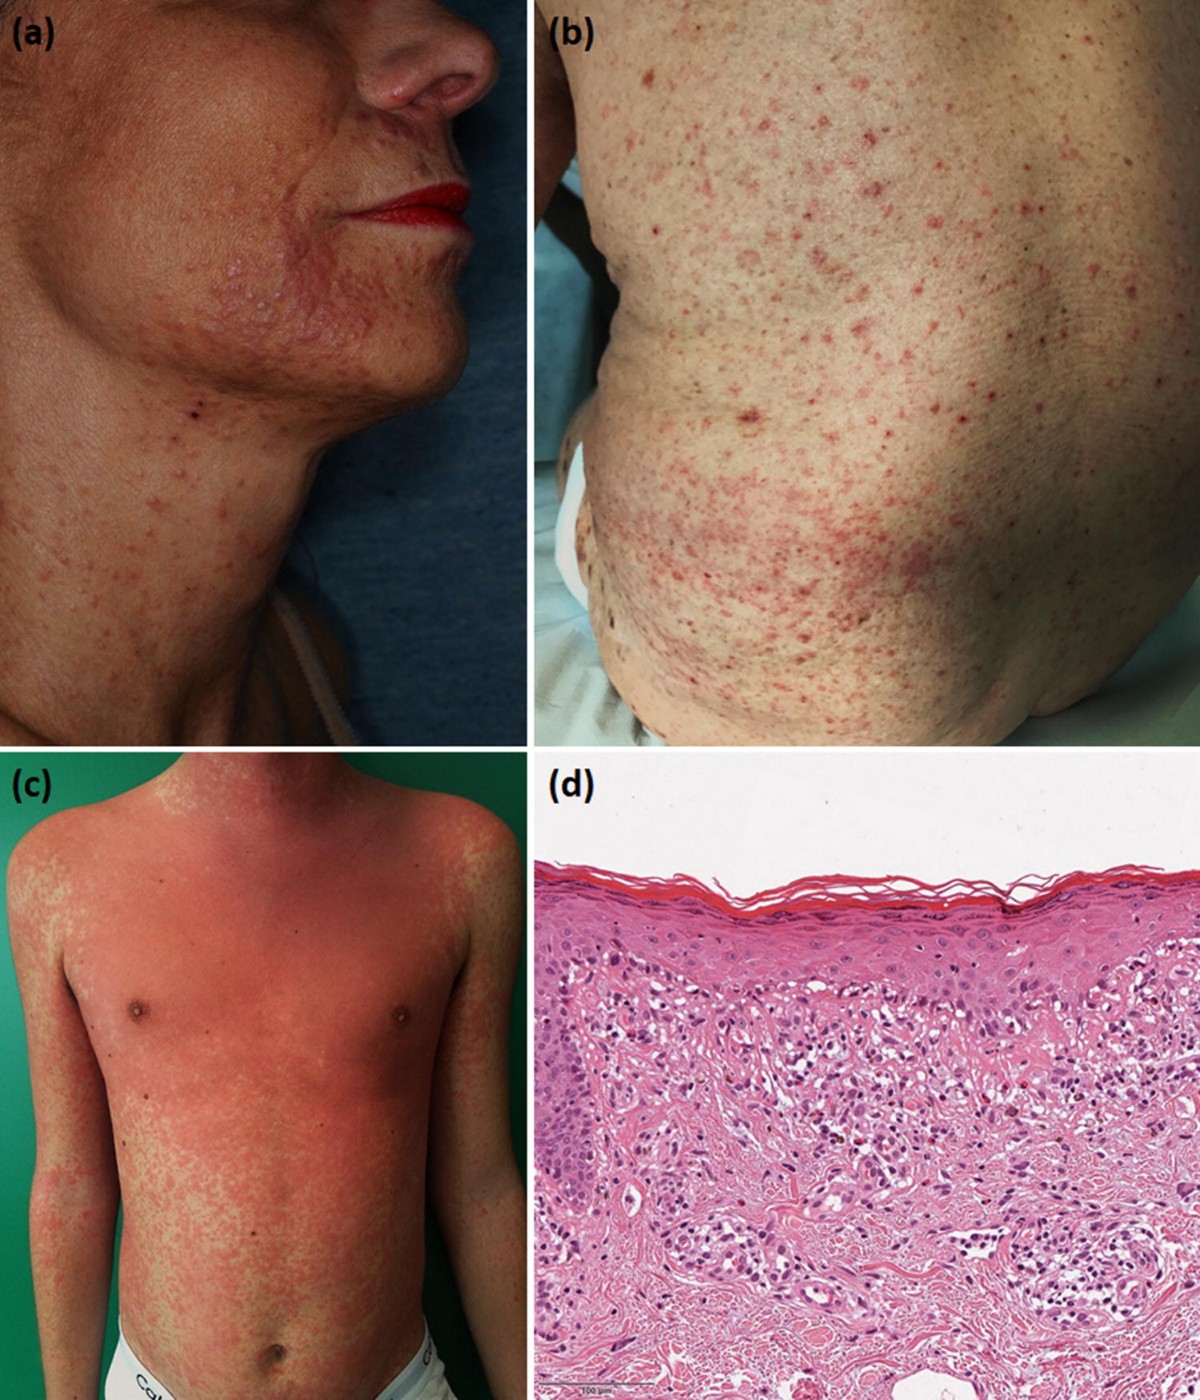

Eosinophilic cellulitis (Wells syndrome) successfully treated with mepolizumab - JAAD Case Reports

image size: 1204x831

Eosinophilic Cellulitis Seems to Be Type 2 Inflammatory Disease - Southern Iowa Mental Health Center

image size: 2000x1435